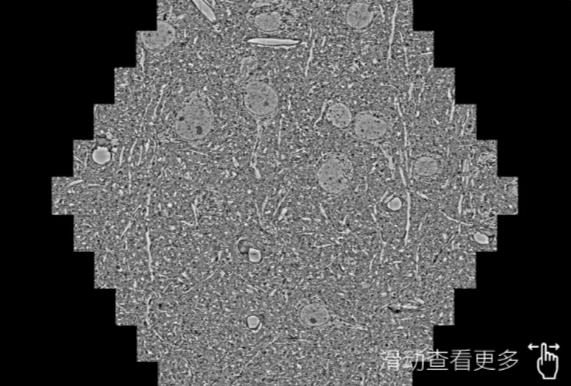

鼠脑切片。左图使用滨州蔡司滨州扫描电镜MultiSEM706对165μmx143pm面积区域成像,耗时仅需1.5秒。右图为鼠脑切片中30μm区域放大效果。样品由芝加哥大学B.Kasthuri提供。

使用蔡司高速滨州扫描电镜MultiSEM对1mm²人脑皮层组织进行高分辨成像,并对其中的各种细胞结构进行三维重构分析。左图展示了2x3mm²组织平面中锥体神经元的三维重构效果。右图显示了局部体积神经元三维重构。图像由哈佛大学chtman实验室提供,渲染图由D. Berger 制作。